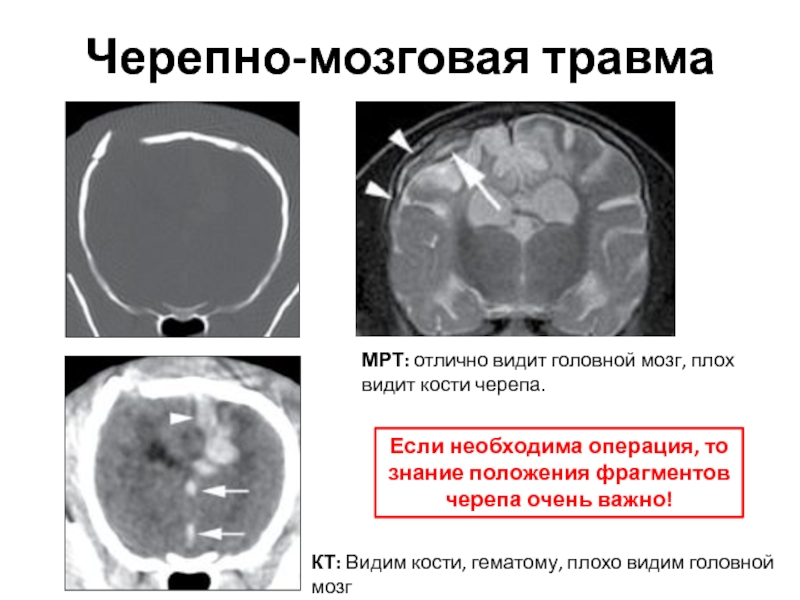

Компьютерная томография в неврологии презентация - 86 фото